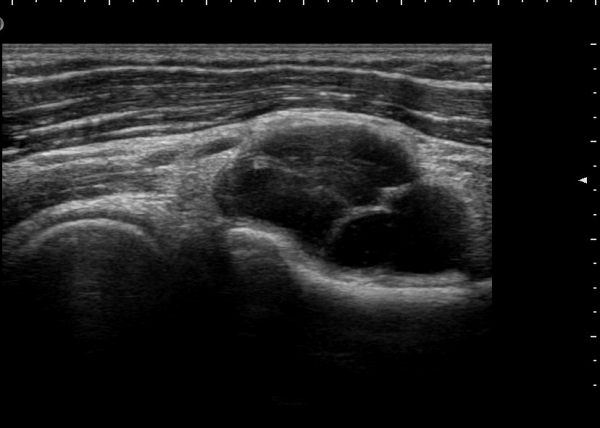

¿ä°ñ½Å°æÀÇ Èİñ°£½Å°æºÐÁö Ⱦ´Ü¸é°Ë»ç¿¡¼­ ¼ÒµÎ Ç¥Ãþ »ó¿Ï±Ù°ú »ó¿Ï¿ä°ñ±Ù »çÀÌ¿¡¼­

½Å°æ ºÐÁö°¡ Àß °üÂûµÈ´Ù(±×¸² 1).